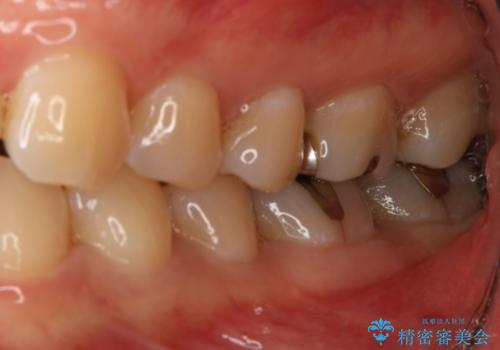

- 左下奥歯のメタルインレーを白くしたいと希望された患者様です。

形態、切削量などを考慮し、セラミックインレーにて治療を行いました。

メタルインレー、う蝕除去後にCRにて裏層した上で、形成・印象を行いました。